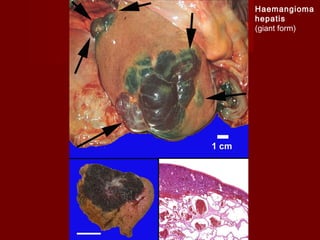

Haemangioma

hepatis

(giant form)